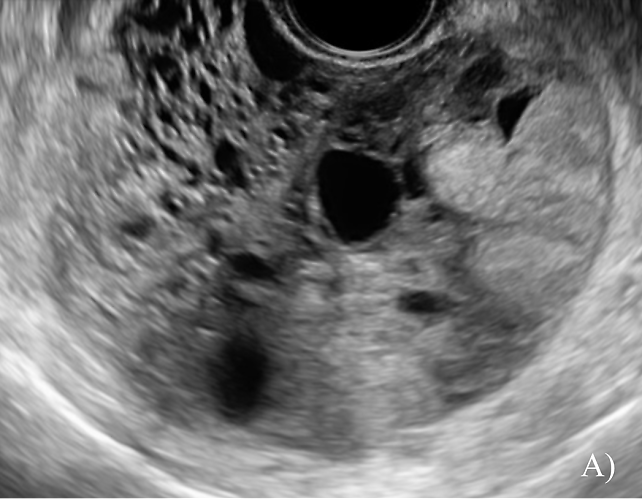

Mucinous BOTs (previously called intestinal type BOTs) are generally multilocular (80%) or unilocular (15%) and are typically large, with a median diameter of 195 mm. They feature multiple small loculi, often resembling a 'honeycomb appearance' and contain low-level cystic fluid without papillations (Figure 3).

3

Grayscale sonographic images of mucinous borderline ovarian tumors, appearing as multilocular cysts. From A) to H) there is an increase in the number of locules, varying from a cyst with <10 locules to a multilocular cyst with a marked honeycomb appearance.